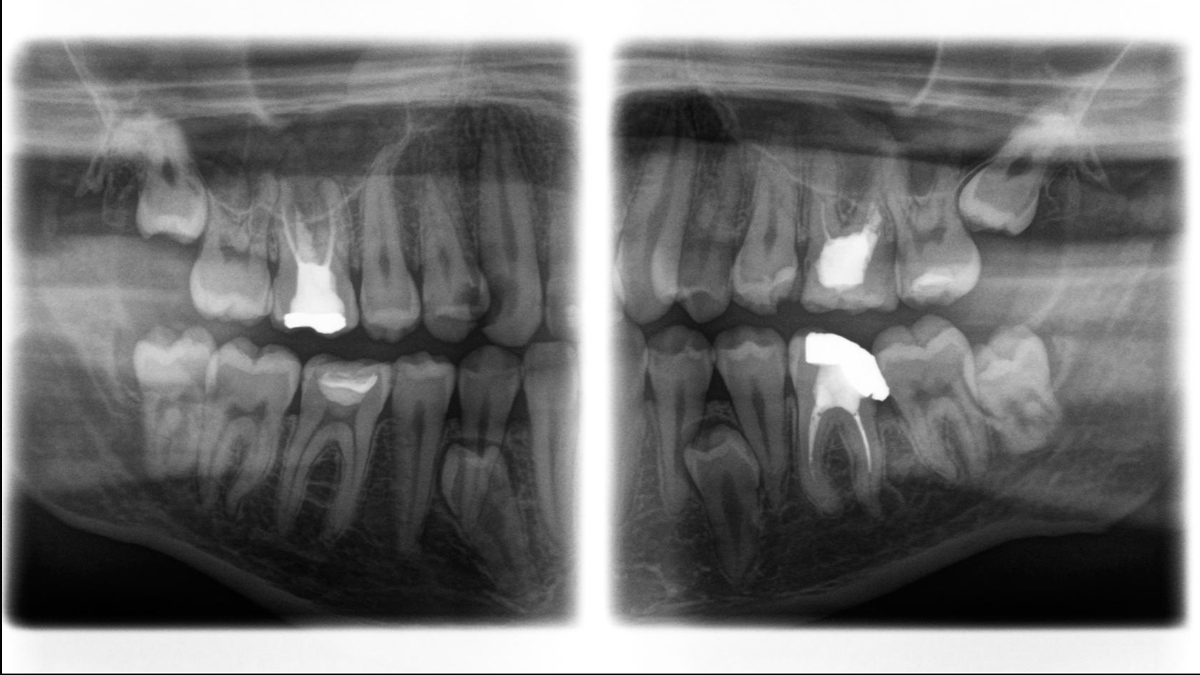

Aunque las radiografías 3D son cada vez más demandadas y existen un gran un número creciente de equipos en consultorios dentales, la imagen 2D sigue teniendo su lugar, en gran medida, debido a su radiación. Las mejoras realizadas en la calidad de imagen hace que las opciones disponibles en tecnología 2D están lejos de haberse agotado. Orthophos SL ha revolucionado la imagen 2D con la introducción del Sensor de Conversión Directa, la tecnología Sharp Layer y la SL interactiva. Experimente imágenes panorámicas como nunca antes.

Galería de muestra de imágenes panorámicas 2D